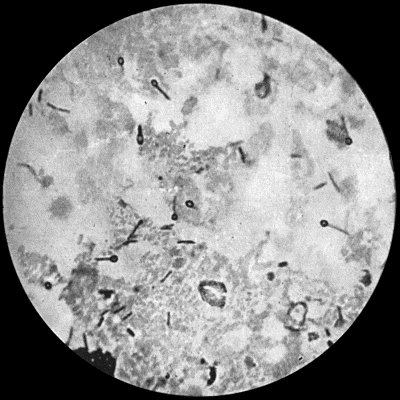

Staphylococcus Aureus.—This is the commonest organism found in localised inflammatory and suppurative conditions. It varies greatly in its virulence, and is found in such widely different conditions as skin pustules, boils, carbuncles, and some acute inflammations of bone. As seen by the microscope it occurs in grape-like clusters, fission of the individual cells taking place irregularly (Fig. 2). When grown in artificial media, the colonies assume an orange-yellow colour—hence the name aureus. It is of high vitality and resists more prolonged exposure to high temperatures than most non-sporing bacteria. It is capable of lying latent in the tissues for long periods, for example, in the marrow of long bones, and of again becoming active and causing a fresh outbreak of suppuration. This organism is widely distributed: it is found on the skin, in the mouth, and in other situations in the body, and as it is present in the dust of the air and on all objects upon which dust has settled, it is a continual source of infection unless means are taken to exclude it from wounds.

Fig. 3.—Streptococci in Pus from an acute abscess in subcutaneous tissue. × 1000 diam. Gram's stain.